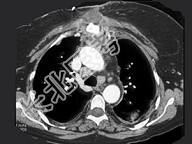

- 单项选择题女,40岁, 高热伴胸痛1周,CT如图, 最可能的诊断是 ( )

A、支气管囊肿

B、淋巴瘤

C、纵隔脓肿伴淋巴结反应性肿大

D、胸腺囊肿

E、恶性畸胎瘤